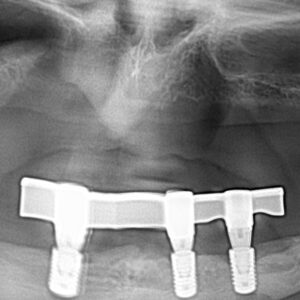

- Bar-retained dentures — A thin metal bar that follows the curve of your jaw is attached to the implants that have been placed in your jawbone. Clips or other types of attachments are fitted to the bar, the denture or both. The denture fits over the bar and is securely clipped into place by the attachment

Lower Jaw Bar Implant Overdentures